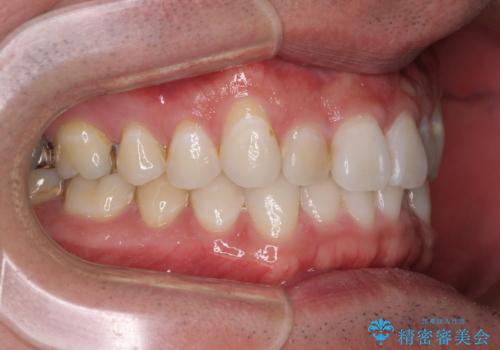

- 上下前歯の叢生を気にして来院された患者様です。

費用を抑え、期間もあまりかけずに治療をしたいとのことで、インビザライン・ライトを用いて矯正治療を行うこととしました。

インビザライン・ライトは、製作できるアライナーの枚数に制限があるため、移動可能な量に限りがあります。

一方で、半年から1年程度で治療を終えることができるため、軽度の歯列不正の患者様には大変お勧めです。